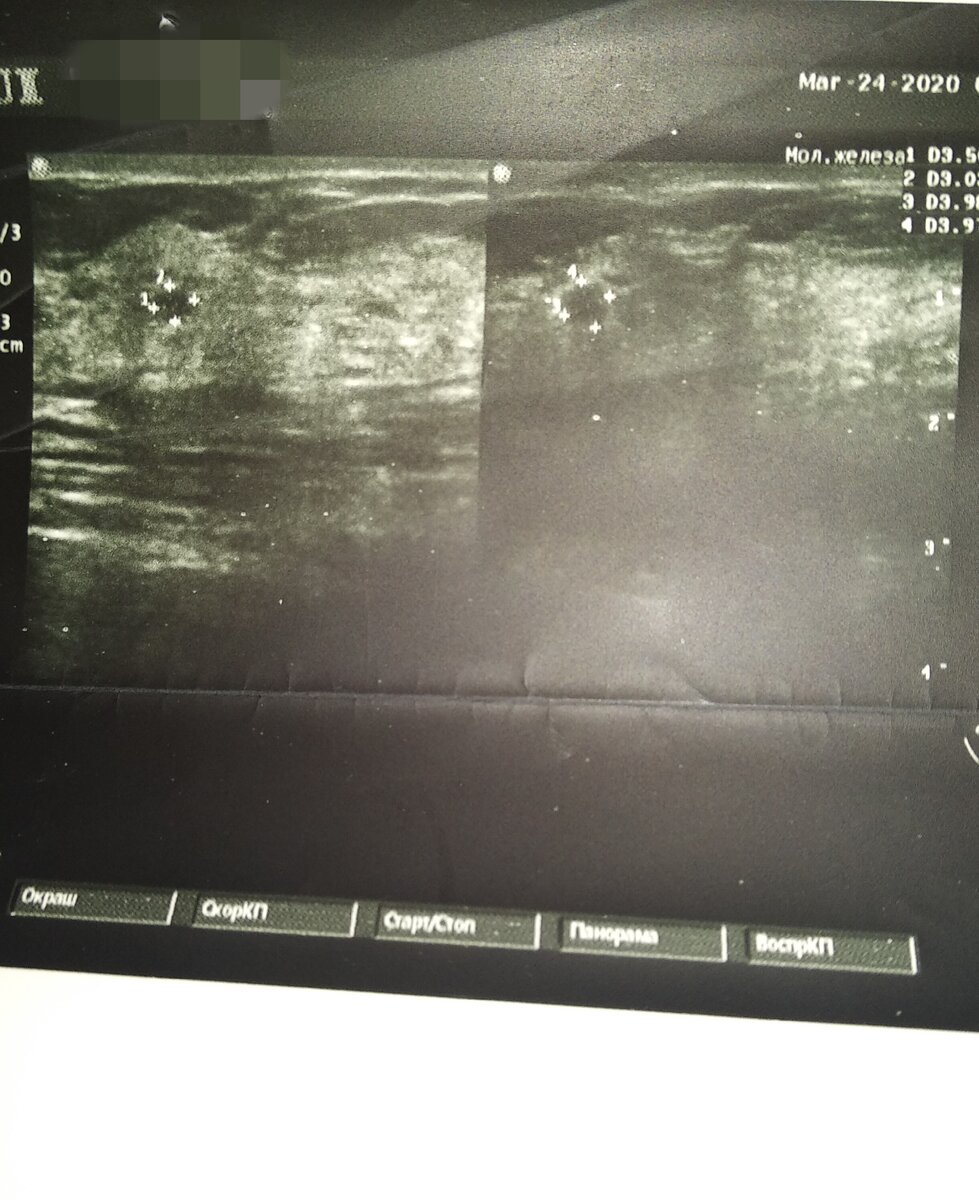

Моя грудь

Вот тут у меня киста